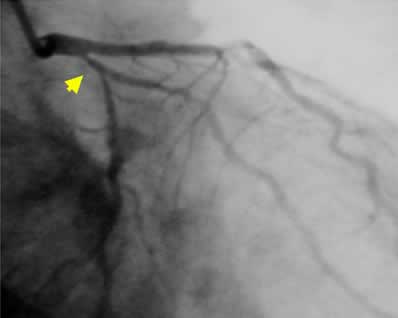

| Final CAG Findings: 01.9.25 LVG: no asynergy, EF: 69% CAG: #11 75% |

![]() Control |

![]() Final

B-3 : 6 months follow-up angio